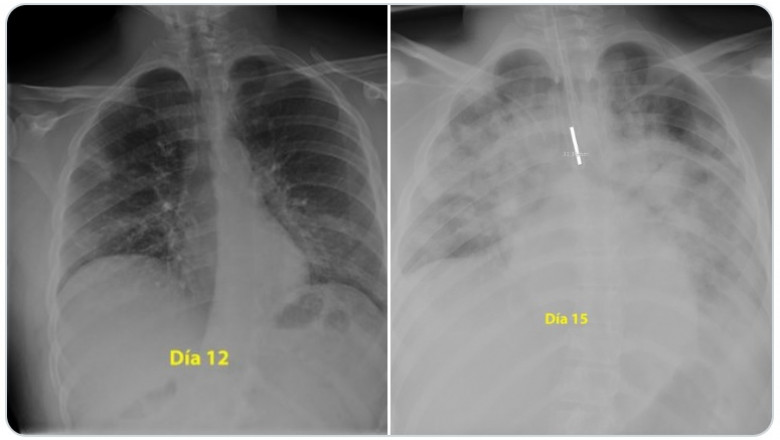

Vedeți mai jos câteva din situațiile în care cred, de fapt sunt sigură, că cei care nu vreți să vă vaccinați și nici măcar să vă testați din banii proprii, vă expuneți copiii și pe voi unor pericole pe care nu aveți cum să le anticipați.